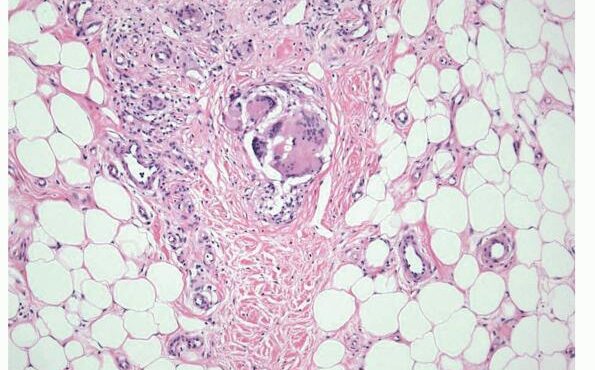

Erythema elevatum diutinum = الحمامى المرتفعة الدائمة Erythema Elevatum Diutinum This rare condition is characterized by persistent, initially red to violaceous and later brown to yellow papules, nodules, and plaques . The lesions, typically distributed symmetrically on the extensor surfaces of the extremities, are initially soft and then evolve into fibrous nodules. Histopathologic Features. In […]